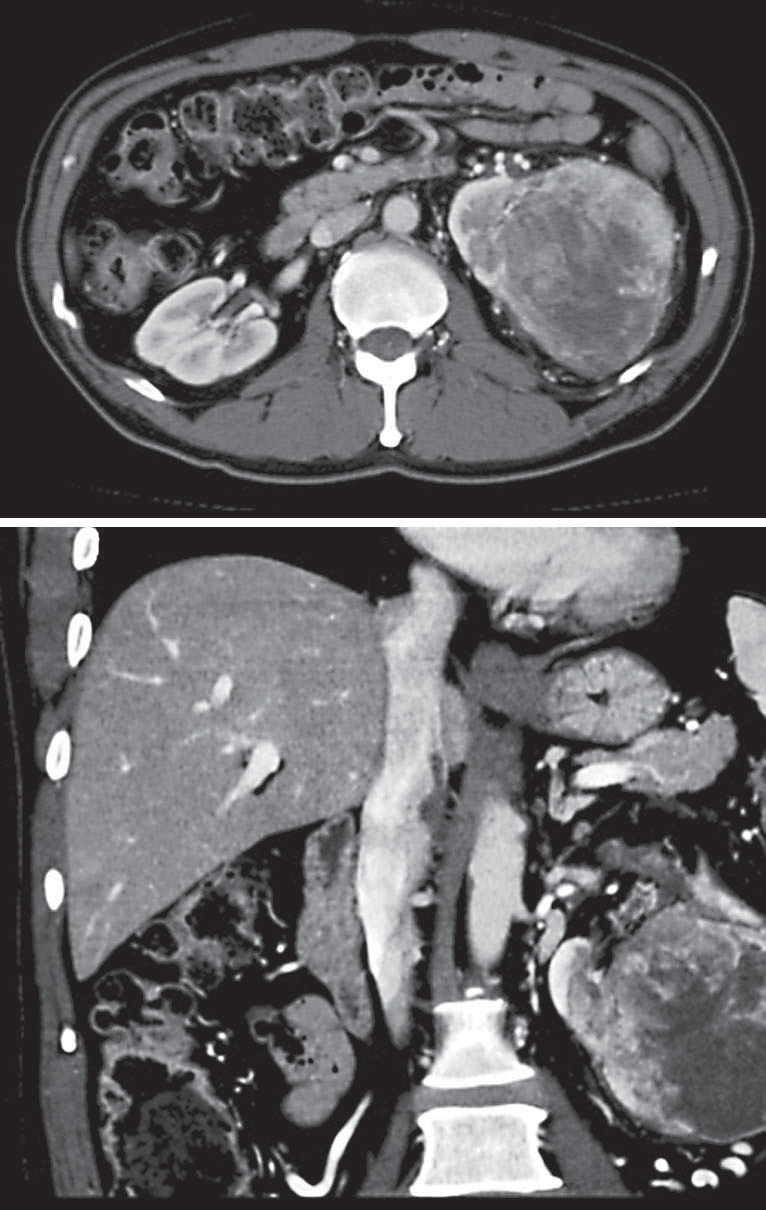

КТ-снимки и строение сосудистой ножки почки